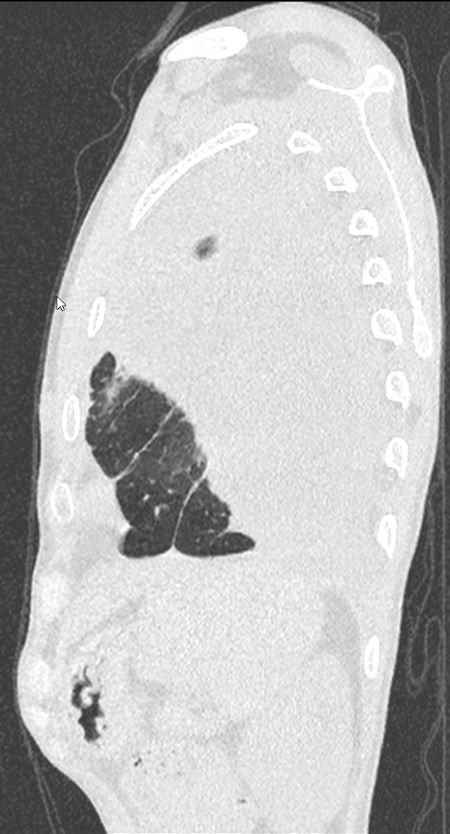

При исследовании в верхушке левого лёгкого было выявлено, субплеврально, полостное образование с толстыми стенками (толщиной до 3,5 мм) с нечёткими и неровными контурами, с прилежанием к костальной плевре на широком основании, размерами 26х22 мм. Вокруг данного образования определялся участок консолидации с прослеживающимися, суженными, деформированными просветами бронхов. Каудальнее образования и участка консолидации определялись хаотично расположенные очаги размером до 7 мм. В S1-2 левого лёгкого субплеврально определялось округлое образование с чёткими, неровными контурами с прилежанием к костальной плевре, размером до 11 мм. В левой плевральной полости жидкостное содержимое с максимальной сепарацией листков плевры до 54 мм, на этом фоне листки плевры были уплотнены, утолщены до 7 мм. На фоне жидкостного содержимого в плевральной полости, в паренхиме левого лёгкого отмечались множественные линейные фиброзные тяжи. В S6, S9 правого лёгкого, перибронховаскулярно, определялись множественные очаги по типу «дерева в почках» (размером до 6 мм), сливающиеся между собой с формированием участка консолидации размером до 27 мм. Кроме того, в правом лёгком определялись множественные мелкие центрилобулярные и субплеварльные очаги уплотнения размером до 4 мм.

Отмечался перелом переднего отрезка 5-го ребра справа с формированием диастаза между отломками до10 мм. В окружающих мягких тканях мелкие костные структуры размером до 2 мм.Заключение

С учетом анамнеза и данных МСКТ-исследования было вынесено заключение КТ-картины полостного образования в верхушке левого лёгкого, с наличием участка консолидации, очагов отсева в верхней доле левого лёгкого, субплеврального образования в верхней доле левого лёгкого, левостороннего плеврального выпота, с признаками утолщения листков плевры, фиброзных изменений левого лёгкого, очагов по типу «дерева в почках» с формированием участка консолидации в нижней доле правого лёгкого (данные изменения, вероятно, соответствуют проявлениям вторичного туберкулёза, дифференцированного с периферическим образованием с признаками вторичных изменений. Перелом переднего отрезка 5-го ребра справа.